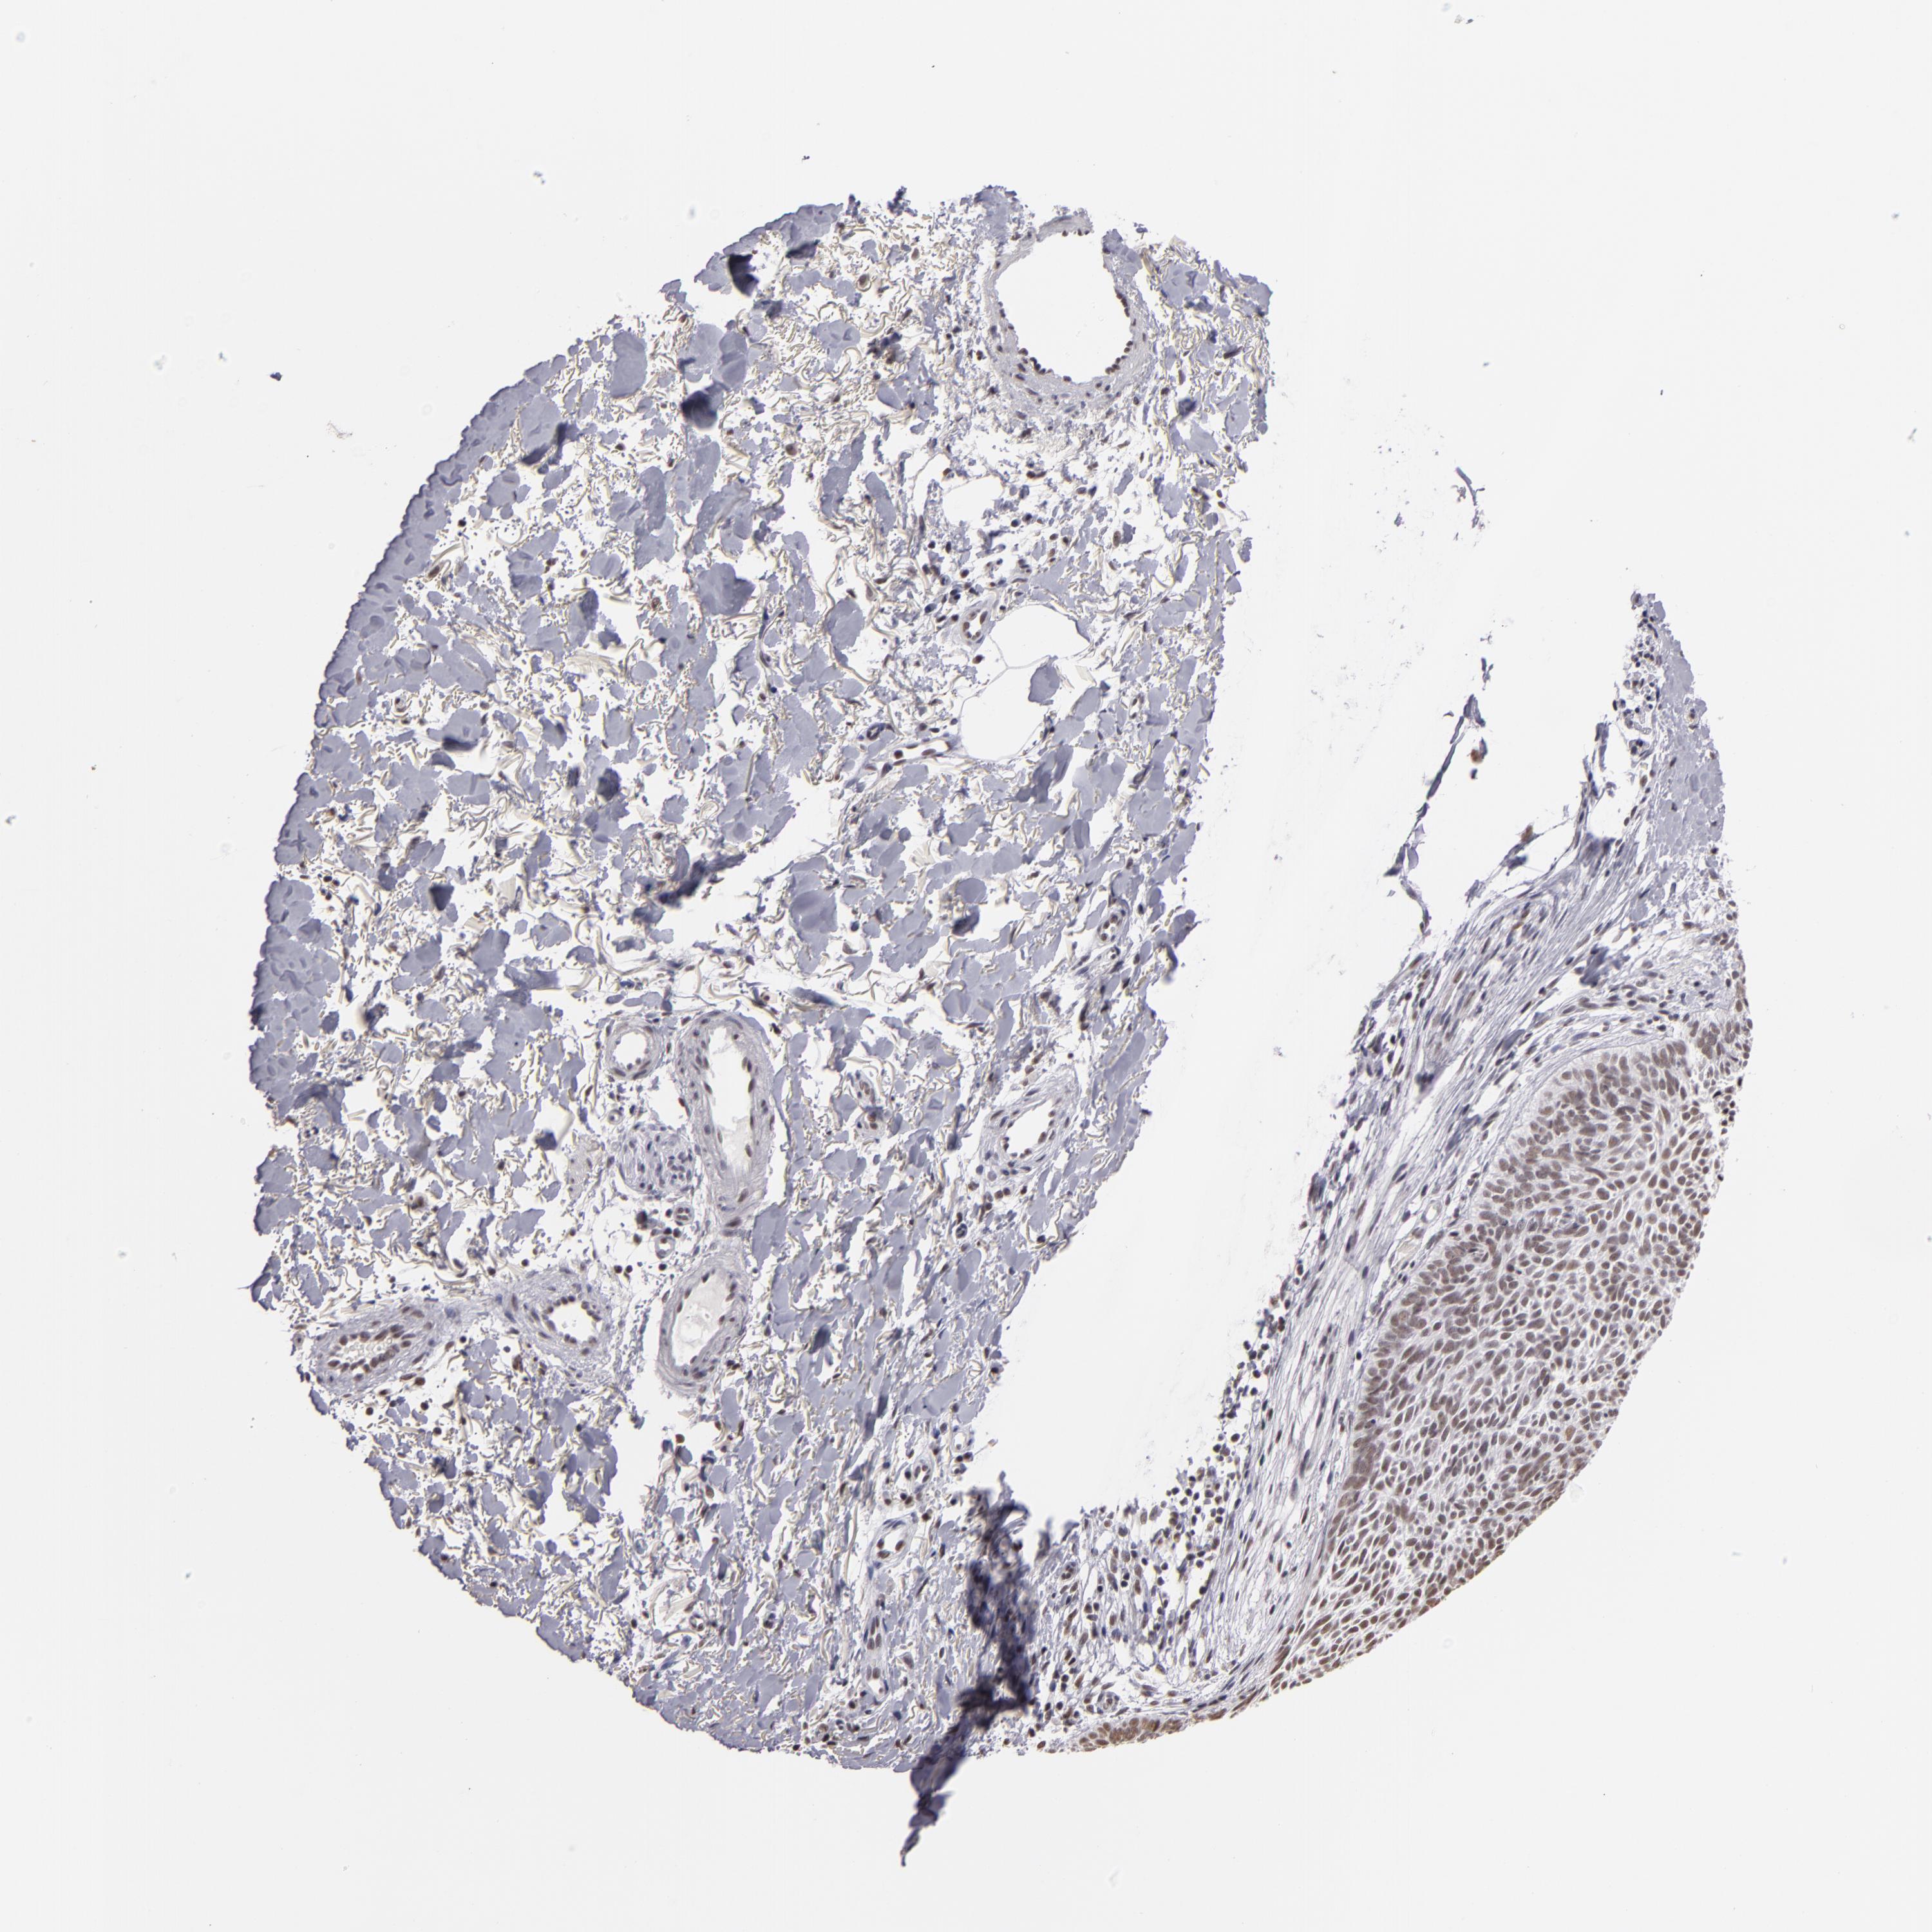

SKIN CANCER - Protein expressioni

A mouse-over function shows sample information and annotation data. Click on an image to view it in a full screen mode. Samples can be filtered based on level of antibody staining by selecting one or several of the following categories: high, medium, low and not detected. The assay and annotation is described here.

Antibody stainingi

Antibody staining in the annotated cell types in the current human tissue is reported as not detected, low, medium, or high, based on conventional immunohistochemistry profiling in selected tissues. This score is based on the combination of the staining intensity and fraction of stained cells.

Each image is clickable and will lead to virtual microscopy that enables deeper exploration of all samples and also displays staining intensity scores, fraction scores and subcellular localization as well as patient and tissue information for each sample.

Antibody HPA001846

Staining

High

Medium

Low

Not detected

Intensity

Strong

Moderate

Weak

Negative

Quantity

>75%

75%-25%

<25%

None

Location

Nuclear

Cytoplasmic/membranous

Cytoplasmic/membranous,nuclear

Basal cell carcinoma